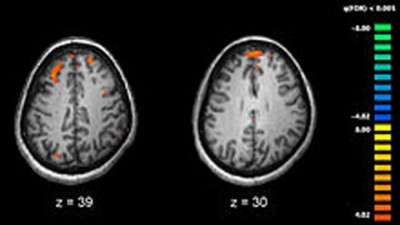

Everyday activities associated with more gray matter in brains of older adults: Study

New York, Feb 26 (IBNS): Higher levels of lifestyle physical activity — such as housecleaning, walking a dog and gardening, as well as exercise — are associated with more gray matter in the brains of older adults, according to a study by researchers in the Rush University College of Nursing. The Journal of Gerontology: Psychological Sciences published the study's findings on Feb. 8.